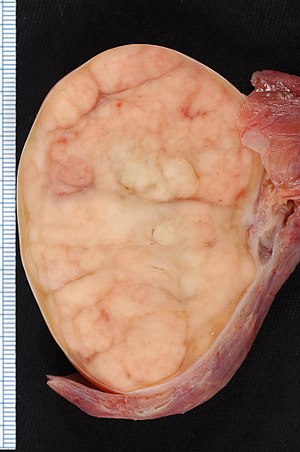

Seminomas (which account for 55 percent of cases) have a great prognosis, late metastasis, and a high radiation treatment response rate.

Large cells with transparent cytoplasm and central nuclei (like spermatogonia) make up the malignant tumor known as a seminoma, which develops as a homogeneous mass without bleeding or necrosis.